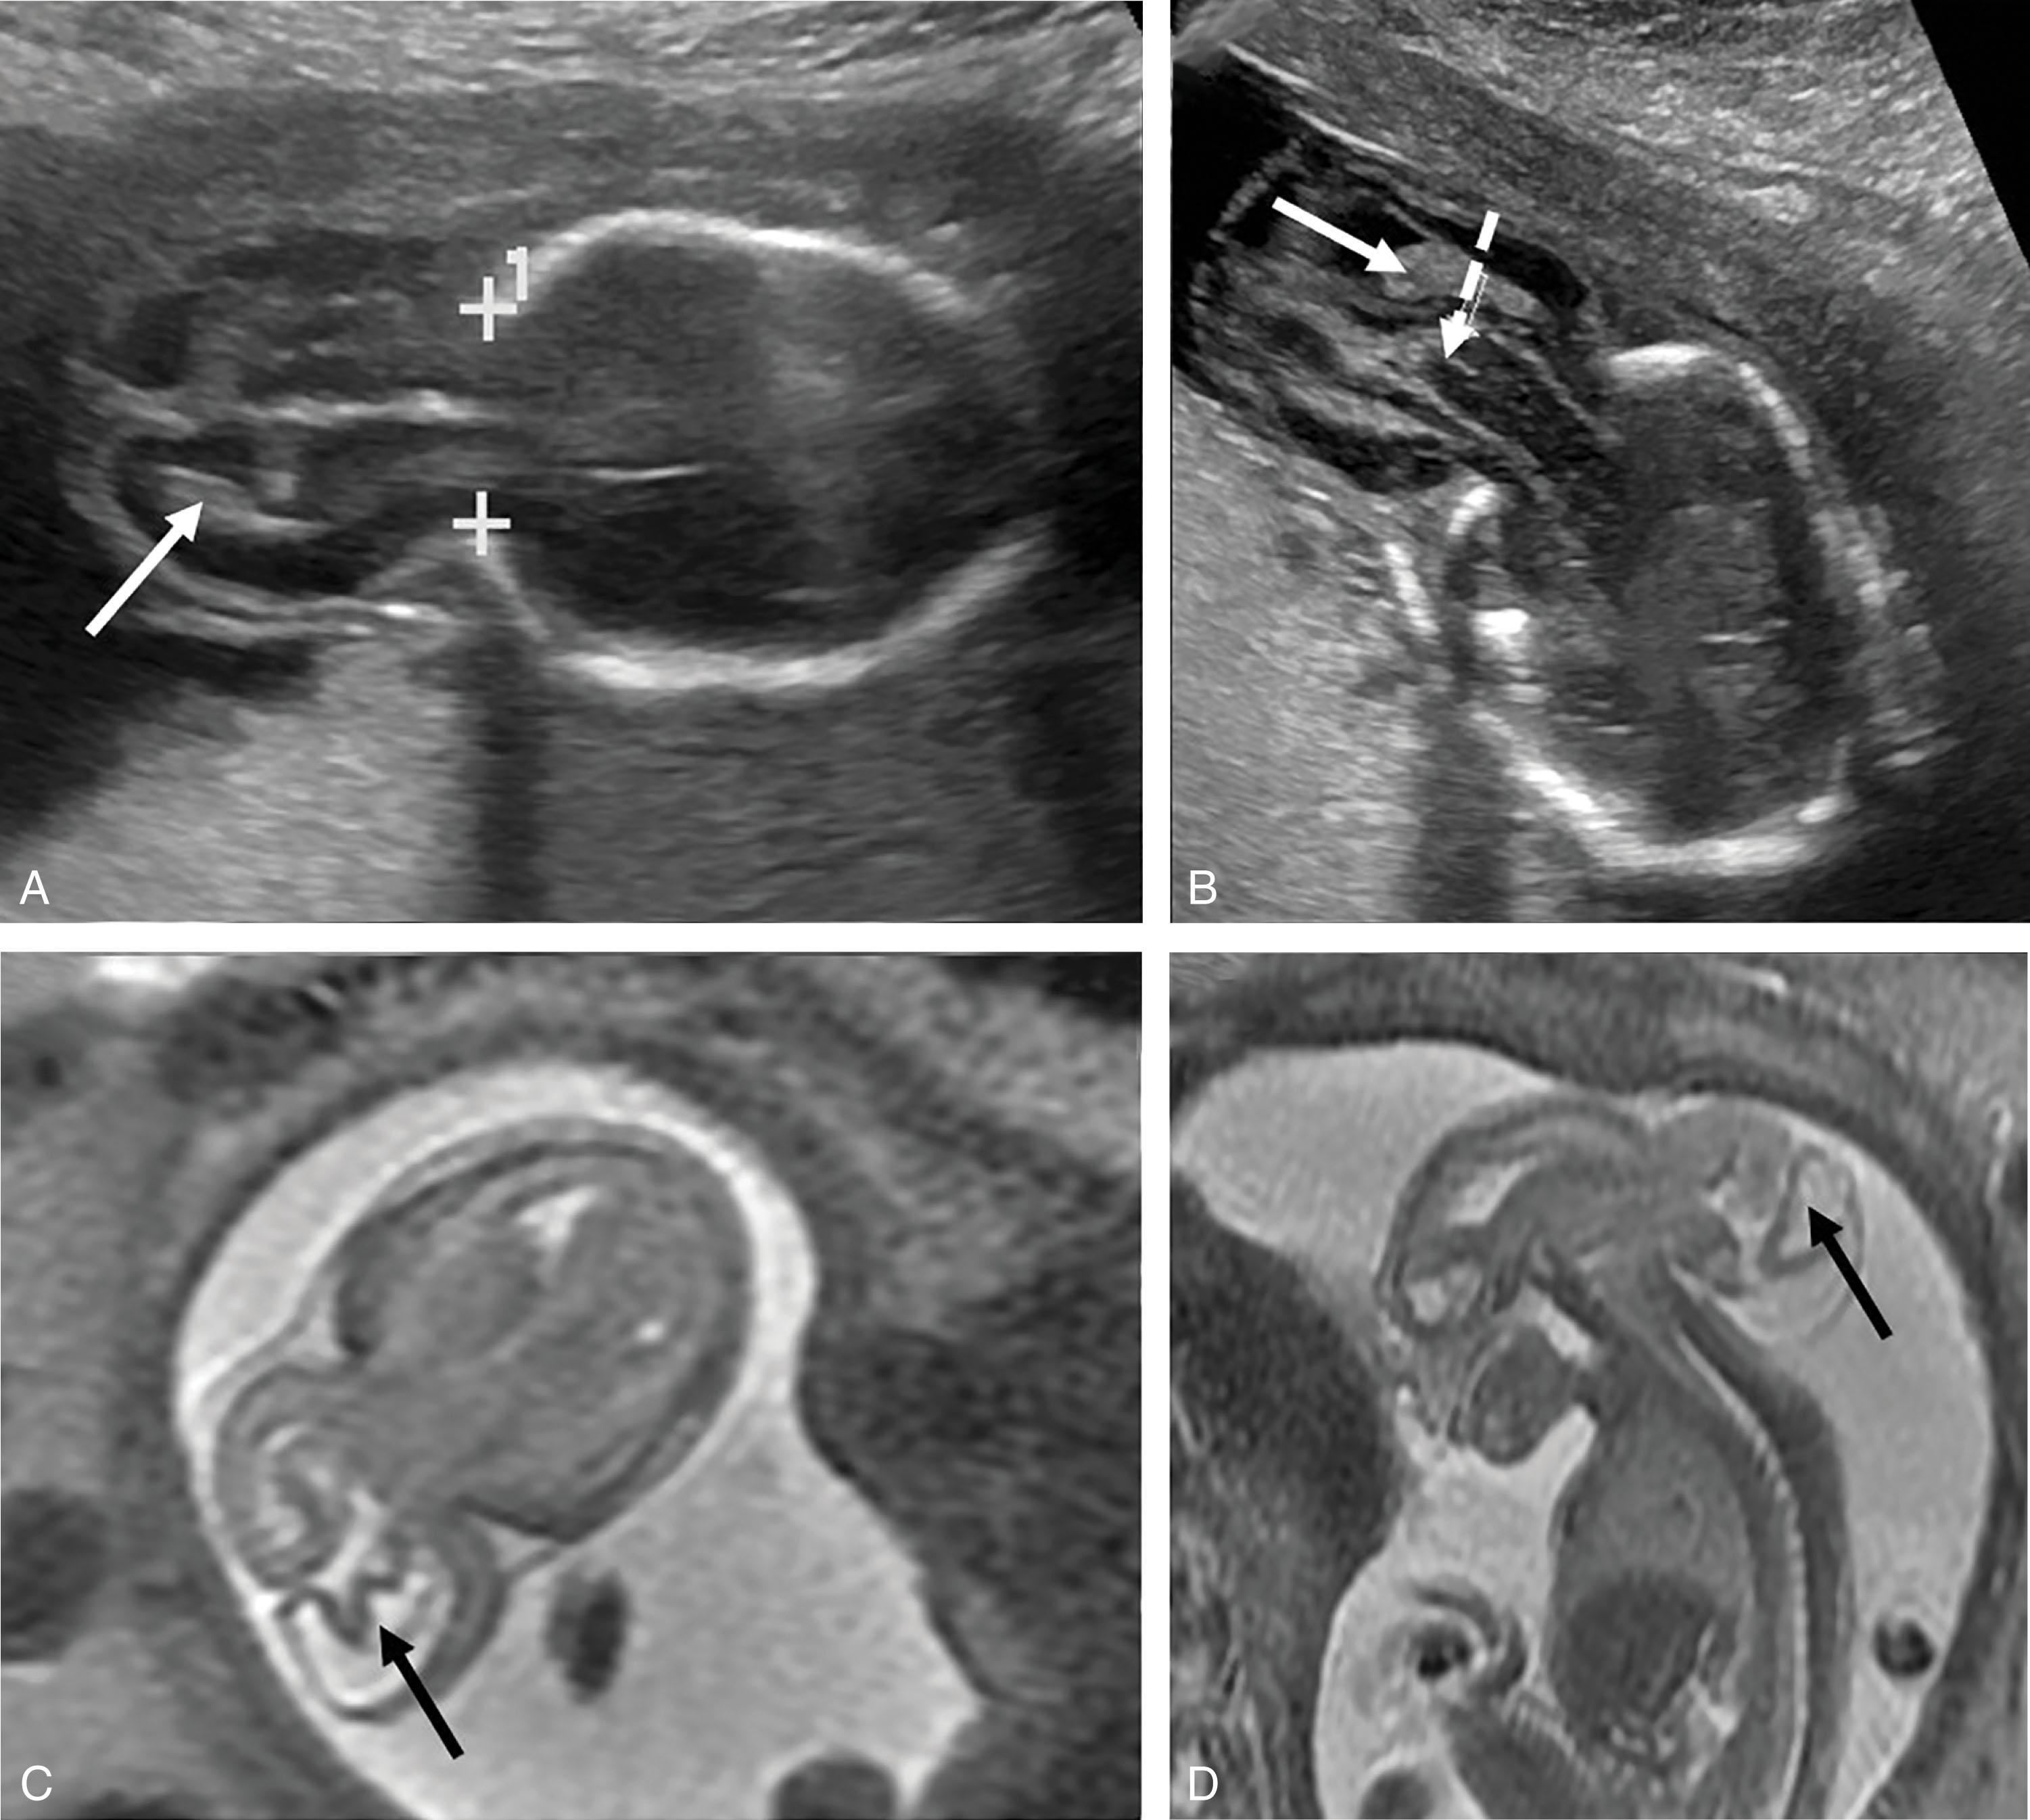

Fig. 1.5, Meningoencephalocystocele. A 22-week gestational age fetus with a large posterior meningoencephalocystocele with herniated occipital, temporal, and parietal lobes; brainstem; cerebellum; and posterior lateral ventricles. Fetal ultrasound (A, B, axial views) and T2-weighted MRI (C, axial view; D, sagittal view). Crosses (A) show cranial defect; white solid arrows (A, B) show choroid plexus; broken white arrow (B) shows herniated brainstem; black arrows (C, D) show lateral ventricles within the herniated brain tissue.